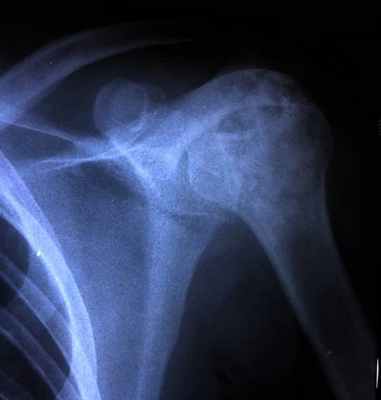

Хондробластома — редкая опухоль, составляет 1–1,8% первичных опухолей кости (10% всех опухолей скелета). Возникает преимущественно в детском и юношеском возрасте. Излюбленная локализация — длинные трубчатые кости. Поражает эпифизы и метафизы (проксимальный и дистальный отделы бедренной кости, проксимальные отделы большеберцовой и плечевой костей), реже — кости таза и лопатки • Клиническая картина. Превалирует боль, отмечается небольшая припухлость, иногда ограничение движений в суставе и гипотрофия мышц • Диагностика. Рентгенологически определяют неоднородный очаг деструкции округлой или овальной формы. Дифференциальную диагностику хондробластомы проводят с солитарной энхондромой и литической формой остеобластокластомы • Лечение хондробластомы хирургическое (кюретаж), однако, учитывая возможность малигнизации, рекомендуют резекцию кости.

(Слева) Рисунок: срез проксимального отдела плечевой кости с типичной хондросбластомой. Показан эпифизарный, эксцентрично расположенный очаг с четкими границами. Патологическое образование имеет склеротический край и содержит кальцинаты.

(Справа) Рентгенография: классическая хондробластома у пациента с почти зрелым скелетом. Литический очаг развивается в эпифизе и распространяется на метафиз. Очаг не содержит кальцинированный матрикс, имеет четкие границы и умеренно склерозированный край. (Слева) МРТ, корональная проекция, режим Т1: однородный, эксцентрично расположенный эпифизарный очаг, типичный для хондробластомы. В зоне метафиза визуализируется массивная периостальная реакция типичный признак в 50% случаев.

(Справа) КТ, аксиальная проекция, без контрастного усиления: весьма эксцентрично расположенная хондробластома эпифиза плечевой кости. Она содержит небольшое вкрапление кальцинированного матрикса и немного вспучивает кортикальный слой. Этому пациенту с жалобами на боль и пощелкивание при ротации плеча, в первую очередь, вместо лучевого исследования, было необоснованно выполнено артроскопическое вмешательство.

Хондробластома – преимущественно доброкачественная опухоль, поражающая в основном эпифизы (головки) и метафизы (шейки) трубчатых костей и формирующаяся из хрящевых клеток. На ее долю приходится 1—4% всех случаев выявления доброкачественных новообразований. Чаще всего она обнаруживается в дистальном эпифизе бедренной кости, несколько реже в проксимальном эпифизе большеберцовой кости, которые формируют колено. Таким образом, в большинстве случаев диагностируется хондробластома коленного сустава. Третьим по частоте поражается проксимальный эпифиз плечевой кости и значительно реже выявляются хондробластомы костей таза, стоп, ребер, позвоночника, лопаток и других трубчатых и плоских костей скелета. Пик диагностирования патологии припадает на период 10—20 лет, намного реже хондробластомы обнаруживаются у людей зрелого и пожилого возраста. Но, что характерно, количество мужчин с таким диагнозом в 1,5—2 раза превышает число заболевших женщин.

На полученных снимках опухоль имеет вид ограниченного, более светлого, чем остальные, участка яйцевидной или круглой формы с четкими, ровными контурами. Зачастую он локализован на боковой поверхности эпифиза пораженной кости. Если хондробластома распространяется в область крепления сухожилий, наблюдается полное разрушение сухожильной пластинки. По краю новообразования визуализируется зона склероза. При этом отмечаются признаки незначительного вздутия кортикального слоя кости, а также могут обнаруживаться периостальные наслоения в области метафизов. Достаточно часто внутри опухоли выявляются вкрапления обызвествления.